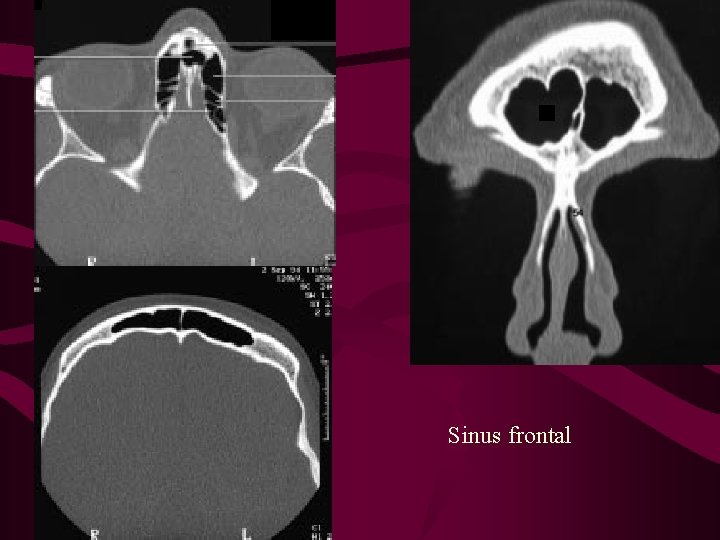

Pathologies du sinus frontal SERVICE ORL DU CHU DE CAEN

Pathologies du sinus frontal SERVICE UNIVERSITAIRE ORL DE CAEN

Une hypoplasie se manifeste par le développement insuffisant d'un organe, d'un tissu ou d'un membre Un sinus frontal hypoplasique est une cavité sinusale sous-développée située au centre du front

Peut survenir avec des symptômes, peut être asymptomatique Approximately 10 percent of all adults have hypoplastic frontal sinuses Frontal sinus is absent bilaterally in 3-4 to 10 % of population